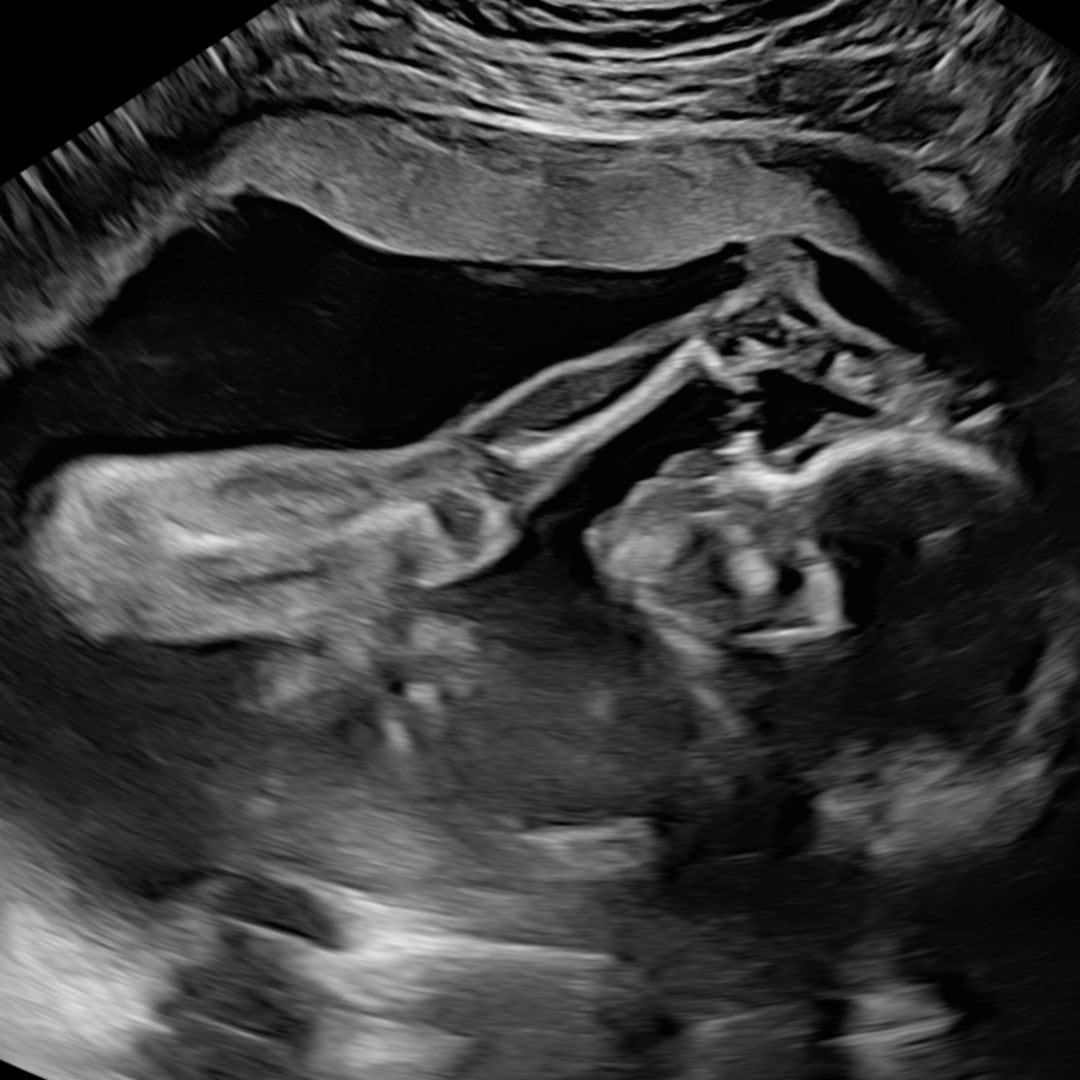

Baby Violet🩷🧸